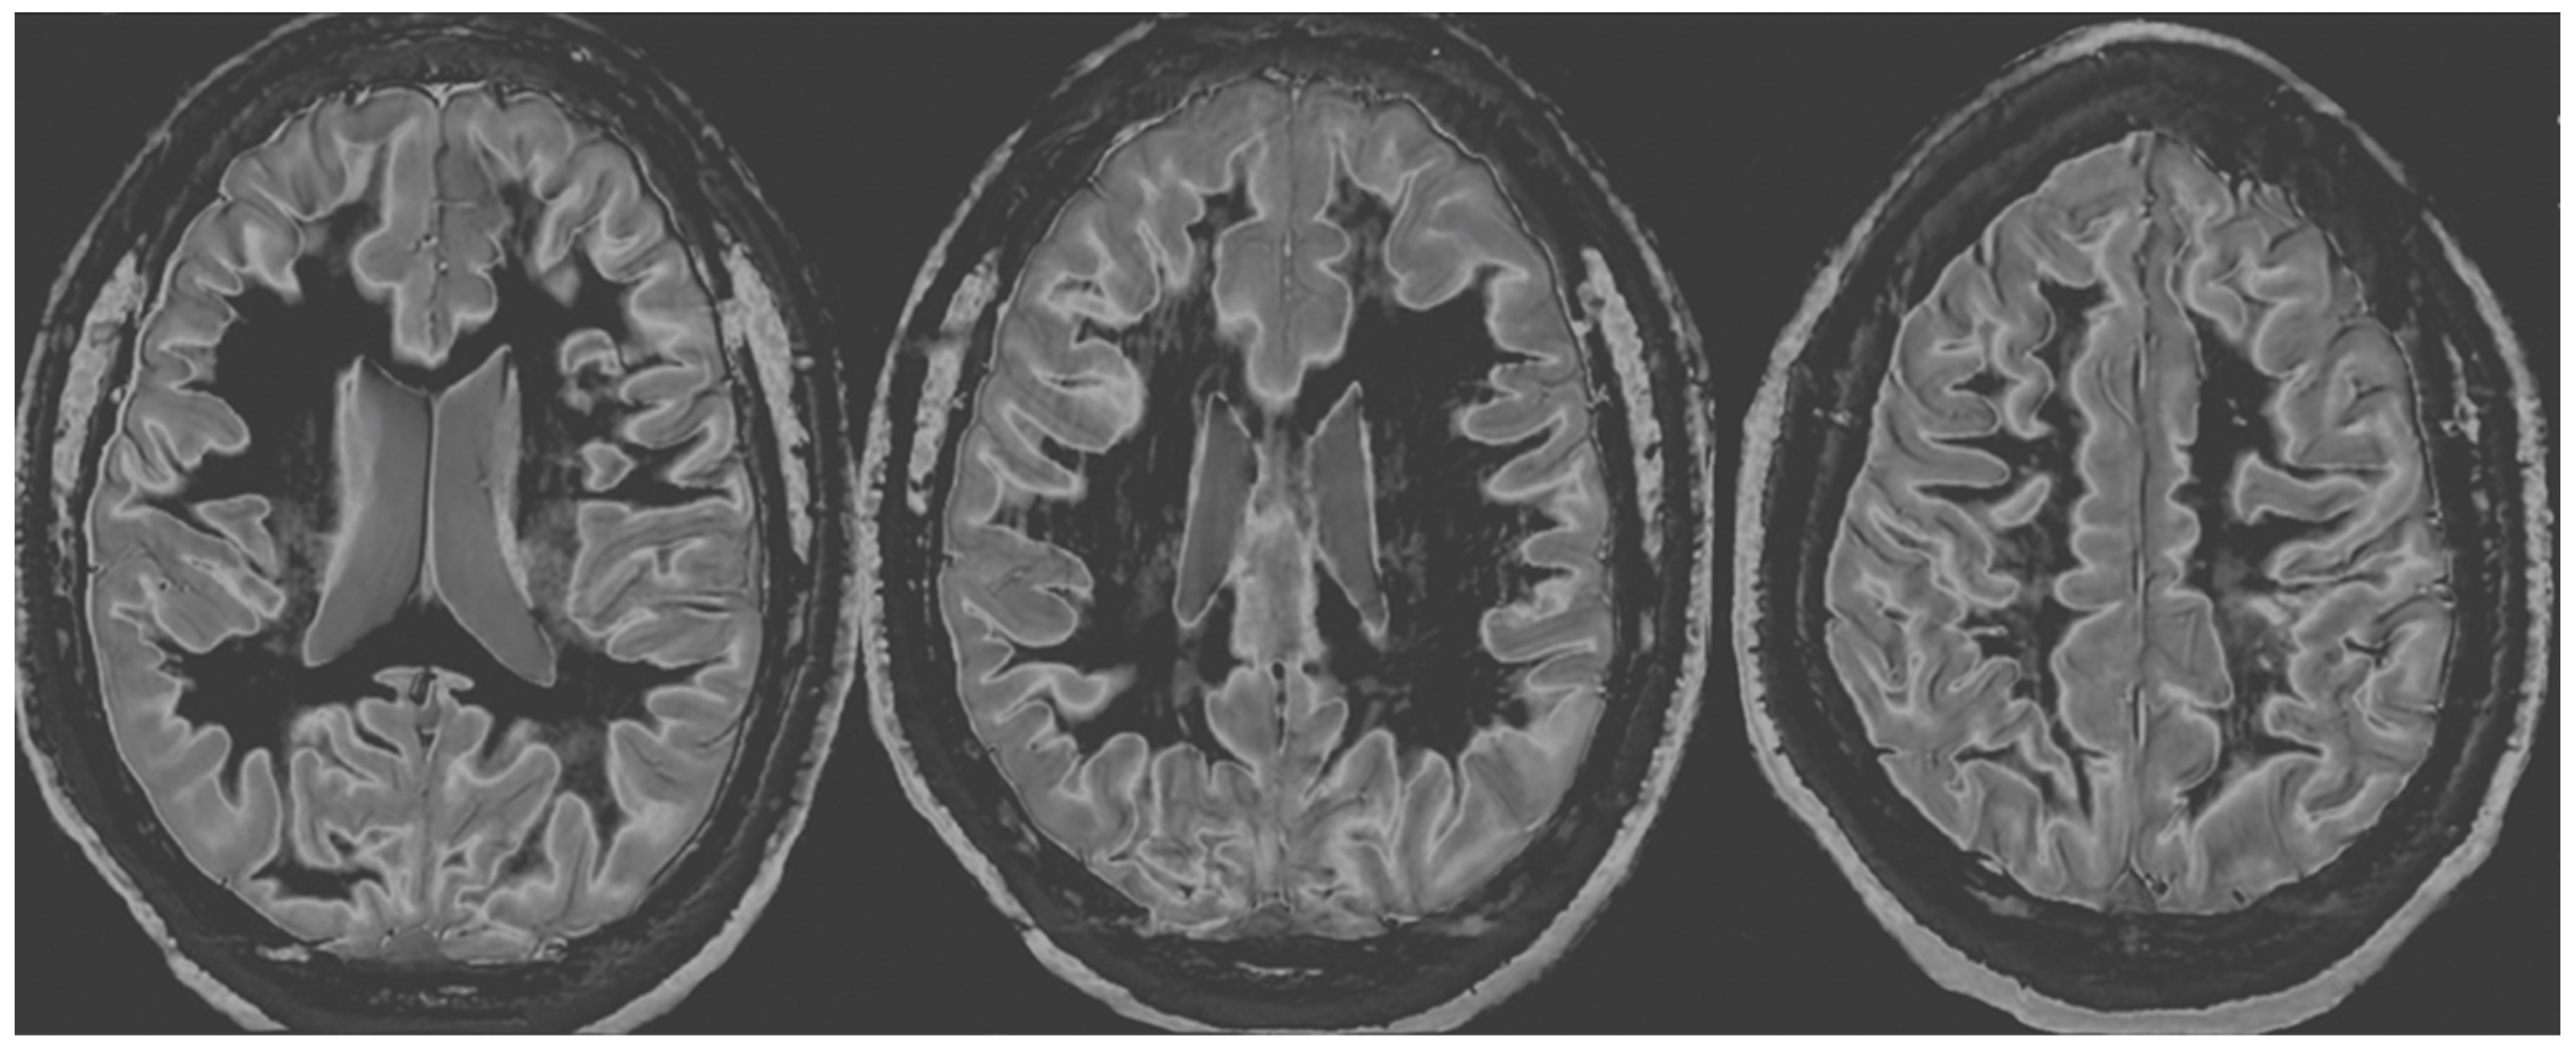

Figure 4 and Figure 5 show T2-FLAIR images (upper rows) with positionally matched dSIR images (lower rows). No abnormality is seen in white matter on the T2-FLAIR images, but very extensive high signal abnormalities are seen in white matter on the corresponding dSIR images. In Figure 4, there is sparing of white matter in the anterior central corpus callosum and adjacent forceps minor, which have a dark appearance (long white arrows). There is also some sparing of the posterior central corpus callosum. In Figure 5, there is sparing of the peripheral white matter of the cerebral hemispheres, which have a dark appearance (long white arrows). Small focal lesions of a relatively increased signal are also seen in the white matter in Figure 5 (grey arrows) on the dSIR images. High signal boundaries between the white and grey matter are seen, but these are less obvious in many areas because of the high signal present in much of the white matter.

Overall, the abnormalities are bilateral and symmetrical and involve most of the white matter of both the cerebral and cerebellar hemispheres. The appearances in the patient are strikingly different from those in the normal control shown in Figure 3, where normal white matter has a low signal (dark appearance), apart from the corticospinal tracts and areas adjacent to them, which are mid-grey.

Figure 4. Case 1 was examined nine months after a severe drug overdose. Comparison of positionally matched T2-FLAIR images (upper row) and narrow mD dSIR images (lower row). No abnormality is seen on the T2-FLAIR image, but there are extensive areas of a high signal in the white matter of the brain. Only the anterior and posterior central corpus callosum and parts of the frontal lobes have a low signal (dark appearance) and look normal on the dSIR images (white arrows) (lower row). High signal boundaries are seen at the junction between the white matter and grey matter but are rendered less obvious in many areas because of the high signal in much of the white matter.

Figure 5. Case 1 was examined nine months after a severe drug overdose. Comparison of positionally matched T2-FLAIR images (upper row) and narrow mD dSIR images (lower row) (higher cerebral hemispheres). No abnormality is seen on the T2-FLAIR images, but there are extensive areas of high signals in the central white matter of the brain (lower row). Only some of the peripheral white matter on the lower images appears dark and looks normal on the dSIR images (white arrows) (lower row). Some other areas of white matter have a mid-grey appearance consistent with a lesser degree of abnormality. Small focal lesions are also seen on the dSIR images (grey arrows) but not on the T2-FLAIR images.